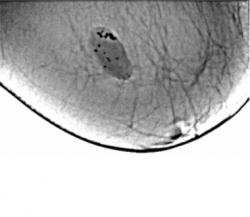

Протокол исследования. В верхнем наружном квадранте инволютивно измененной молочной железы (в годы климакса) определяется тень значительных размеров, овальной формы, средней интенсивности, неоднородной структуры с довольно ровными контурами – фиброаденома. На фоне тени фиброаденомы определяются полиморфные и различные по величине известковые включения. В параареолярной области определяется тень круглой формы средней интенсивности, однородной структуры с ровными контурами – мелкая фиброаденома. Представленные снимки во вложенных файлах (см. ниже). 1 – снимок в прямой проекции; 2 – снимок в боковой проекции; 3, 4 – участки с патологическим образованием, выделенные «навигатором» для более детального анализа. 5- «кальцинат», выделенный навигатором – структура кальцината неоднородная.

Заключение: Инволютивная молочная железы в годы климакса. Фиброаденома крупных размеров левой молочной железы с локализацией в верхнем наружном квадранте с известковыми включениями. Фиброаденома в параареолярной области.